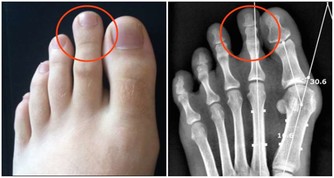

其實早在2011年,類似的案例也發生過。當時一名44歲的紐西蘭女性因為左臂麻痺而被送往醫院,

醫生剛開始完全找不出原因,直到他們發現她的右側脖子上有瘀血,底下的動脈也受損。

該名女性後來因中風而導致部分癱瘓。

當時為她治療的Teddy Wu醫生說:「據我的了解,這是第一次有人因吻痕而送醫。」

這種狀況是因為吻痕導致脖子的主要動脈受損,產生血栓後流至心臟導致中風。

當時這名女性被施打抗凝血素華法林,讓血栓在一週內成功消失。